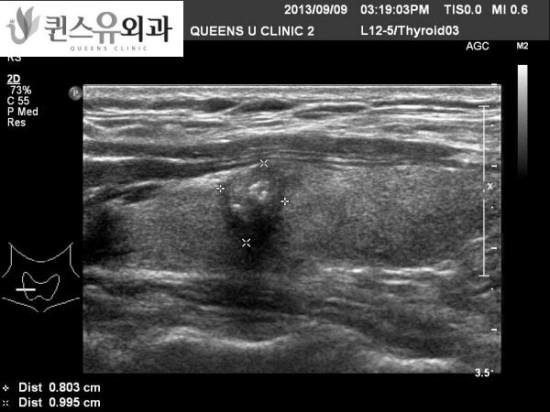

내원하신 환자의 초음파 사진 2

이 환자의 경우 경부 림프선의 전이 수가 많고 왼쪽 갑상선암도 크기가 커서 예후가 좋지 않은 암이 아닐까 생각했는데 다행히 유두암으로 나왔습니다.

환자에게 물어보니 한 10년 전쯤에 갑상선 초음파 검사를 한 번 하고 나서 잊고 있었다고 하셨죠.한 번씩 검진을 해 볼 생각을 하지 못했다고 해서 매우 아쉬워했습니다.